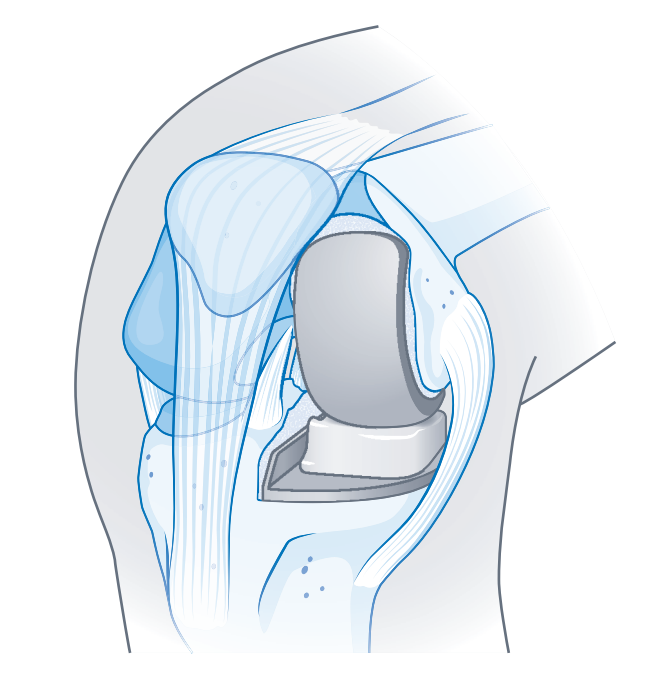

Teilersatz

Ein Teilersatz ist möglich, wenn nur ein Abschnitt des Kniegelenks betroffen ist, die übrigen Gelenkabschnitte unbeschädigt sind und der Bandapparat einschließlich der Kreuzbänder intakt ist; in diesem Fall wird ausschließlich der betroffene Gelenkabschnitt ersetzt.